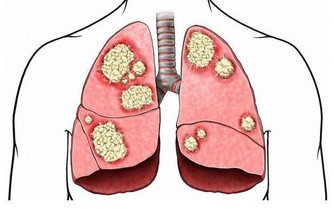

6、頻發炎症

經常咳嗽,容易出現支氣管炎、咽喉炎、肺炎等炎症;如果是本身有哮喘的人,哮喘也會反復發作。